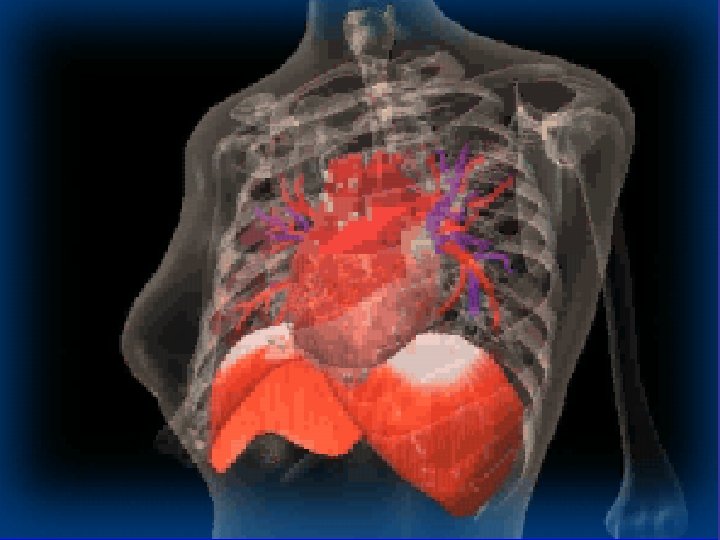

* trachea ; position & caliber * hila : lymphadenopathy * mediastinum contour

* trachea ; position & caliber * hila : lymphadenopathy * mediastinum contour : ? mass * heart : cardiac configuration Mediastinum, heart and hila

How to read a chest x ray ? • 1 - chest wall, bones and abdomen * bones; lesions or fractures * soft tissue ; mastectomy or soft tissue tumors • 2 - heart and mediastinum * trachea ; position & caliber * hila : lymphadenopathy * mediastinum contour : ? mass * heart : cardiac configuration • 3 - lungs opacity or lucency